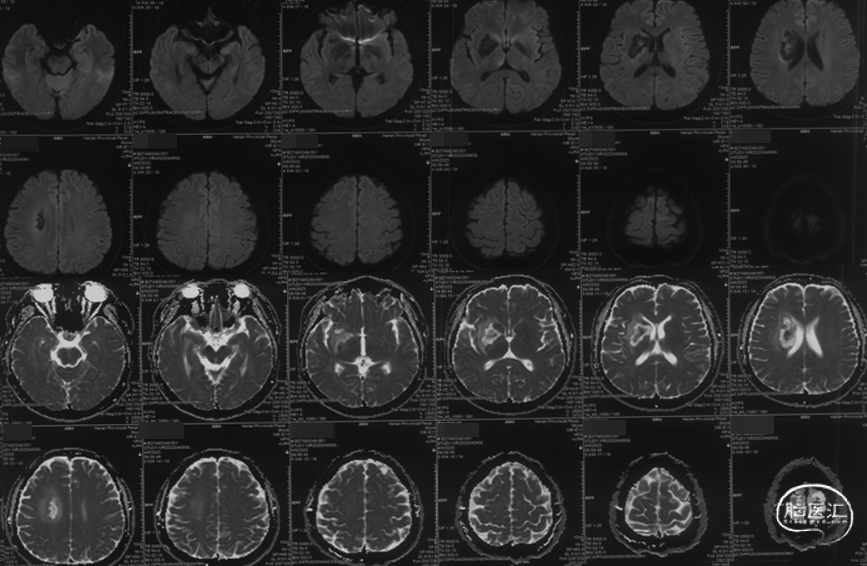

MRI提示右侧基底节区亚急性脑梗死 。

MRA提示右侧大脑中动脉M1段局限性重度狭窄。

CTA提示右侧大脑中动脉局部充盈缺损。

入院后DSA提示右侧大脑中动脉充盈缺损,考虑夹层可能大。